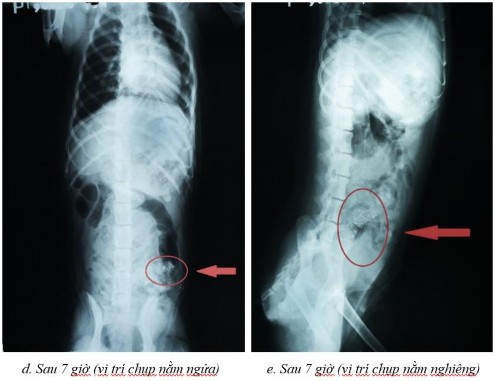

Một số dữ liệu đánh giá sự dịch chuyển in vivo trong đường tiêu hóa chó bằng phương pháp hình ảnh x-quang

Phụ lục 5.1. Hình ảnh X-quang chó 2 ở thời điểm (a) sau 2 giờ ở vị trí nằm nghiêng, (b) sau 4 giờ ở vị trí nằm ngửa, (c) sau 4 giờ ở vị trí nằm nghiêng, (d) sau 7 giờ ở vị trí nằm ngửa, (e) sau 7 giờ ở vị trí nằm nghiêng, (f) sau 9 giờ ở vị trí nằm ngửa, (g) sau 9 giờ ở vị trí nằm nghiêng, (h) sau 11 giờ ở vị trí nằm ngửa và (i) sau 11 giờ ở vị trí nằm nghiêng